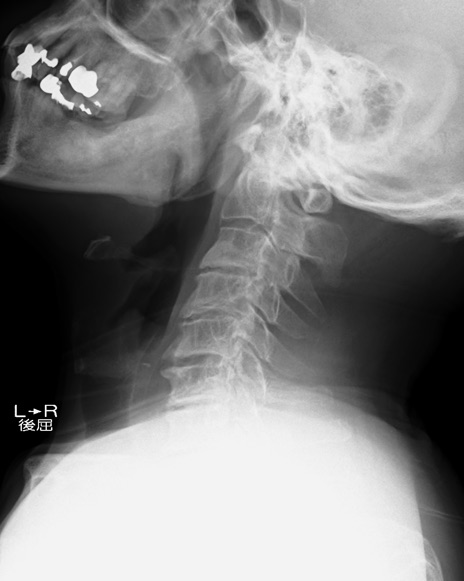

【整形】TIPS症例7 頚椎レントゲン 側面像(伸展)

側面像(屈曲)